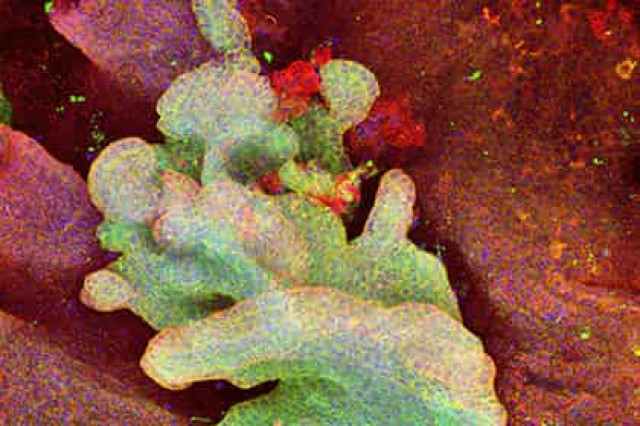

Ученые активировали онкоген — ген, способствующий возникновению опухоли, — в стволовых клетках и незрелых клетках кожи. Оказалось, что клетки-предшественники могут развиваться в доброкачественные опухоли, а стволовые — в злокачественные. Для своих исследований физиологи воспользовались трансгенными мышами, в которых легко можно было включить онкоген. К последнему была дополнительно присоединена флуоресцентная метка, которая позволяла отслеживать потомство клетки, где был активирован онкоген.

Анализируя количество флуоресцентных клеток с использованием математического моделирования, ученые показали, что только потомство мутантных стволовых клеток смогло преодолеть механизм, известный как апоптоз — запрограммированную клеточную гибель — и продолжало бесконтрольно делиться, образуя базально-клеточную карциному.